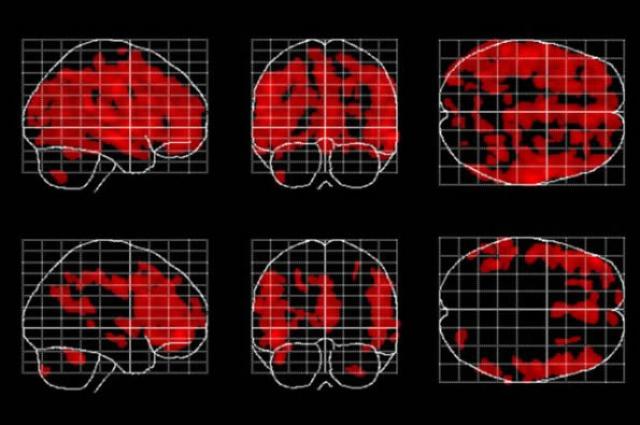

Áreas do cérebro afetadas pelo envelhecimento (em vermelho) estão presentes em menor quantidade e são menos espalhadas em pessoas que meditam (linha inferior) que em pessoas que não meditam. Cortesia: Dr. Eileen Luders / UCLA

Através da comparação dos cérebros de pessoas que meditam com um grupo de controle que não praticava meditação, verificou-se diferença em cinco áreas do cérebro*. Em quatro delas houve aumento de volume: